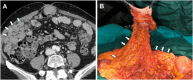

Management of peritoneal surface malignancies is currently entrusted to a multimodality approach. Computed tomography (CT) scan remains the first imaging method despite the limitations in identifying small implants in critical regions. Magnetic resonance imaging is usually recommended for its performance in small implants, mesentery, and small bowel assessment. Positron emission tomography/CT plays an important role only in pseudomyxoma peritonei. Thus, becoming aware of the imaging strengths and drawbacks and having a multimodality imaging approach might be the best option for the patients.